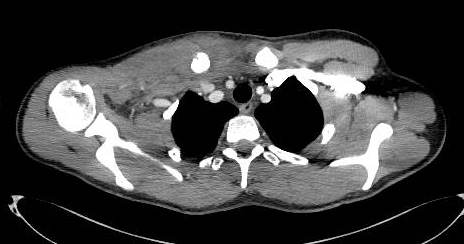

A Contrast CT with 3D CT reconstruction scan (Fig. 2, 3), confirmed the alignment of the floating fragment (rotated and with its medial end pointing posteriorly), which was causing compression on the right Brachiocephalic vein.

Fig. 3: Three-Dimensional Contrast CT Reconstruction

As our experience teaches, a correct and complete pre-operative evaluation (SC dislocations versus fractures; potential compromise of respiratory, neurovascular or other neighbouring structures) should be performed. Contrast CT imaging with three-dimensional reconstruction yields adequate information regarding neighbouring vasculature and alignment of the floating fragment [4, 5, 17], and is the modality of choice in an emergency setting. MRI, if available, and ultrasound imaging would in theory be ideal for the demonstration of articular and physeal anatomy and damage [5], and would have helped us in planning surgery better. Yet, direct surgical visualisation during open reduction provided similar information.